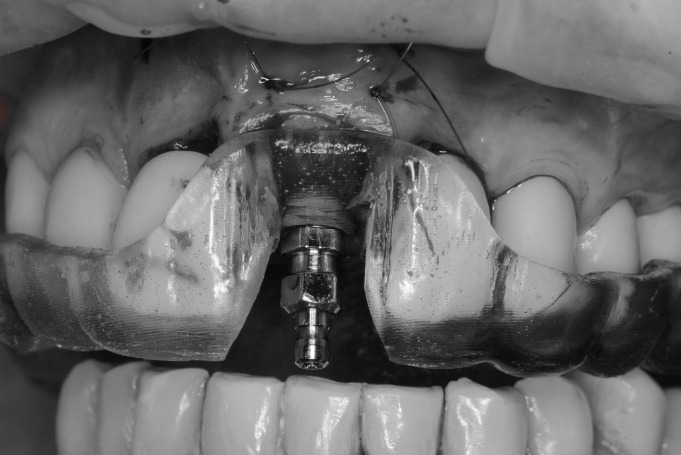

Hoy compartimos un impresionante caso clínico de cirugía guiada, ilustrado con fotos que documentan cada etapa del proceso. En el mismo día, removimos el diente dañado, realizamos injertos de tejido blando y hueso, colocamos el implante y un diente provisional. Como puedes ver en la última foto, el diente provisional se mimetiza perfectamente con los dientes naturales del paciente.

Este procedimiento se llevó a cabo de manera muy controlada y pausada, gracias a la cirugía guiada. Utilizamos una guía quirúrgica protésicamente planificada, que nos permite operar con una precisión excepcional, minimizando cualquier margen de error. Esta técnica es mucho más minuciosa y precisa en comparación con los métodos tradicionales.